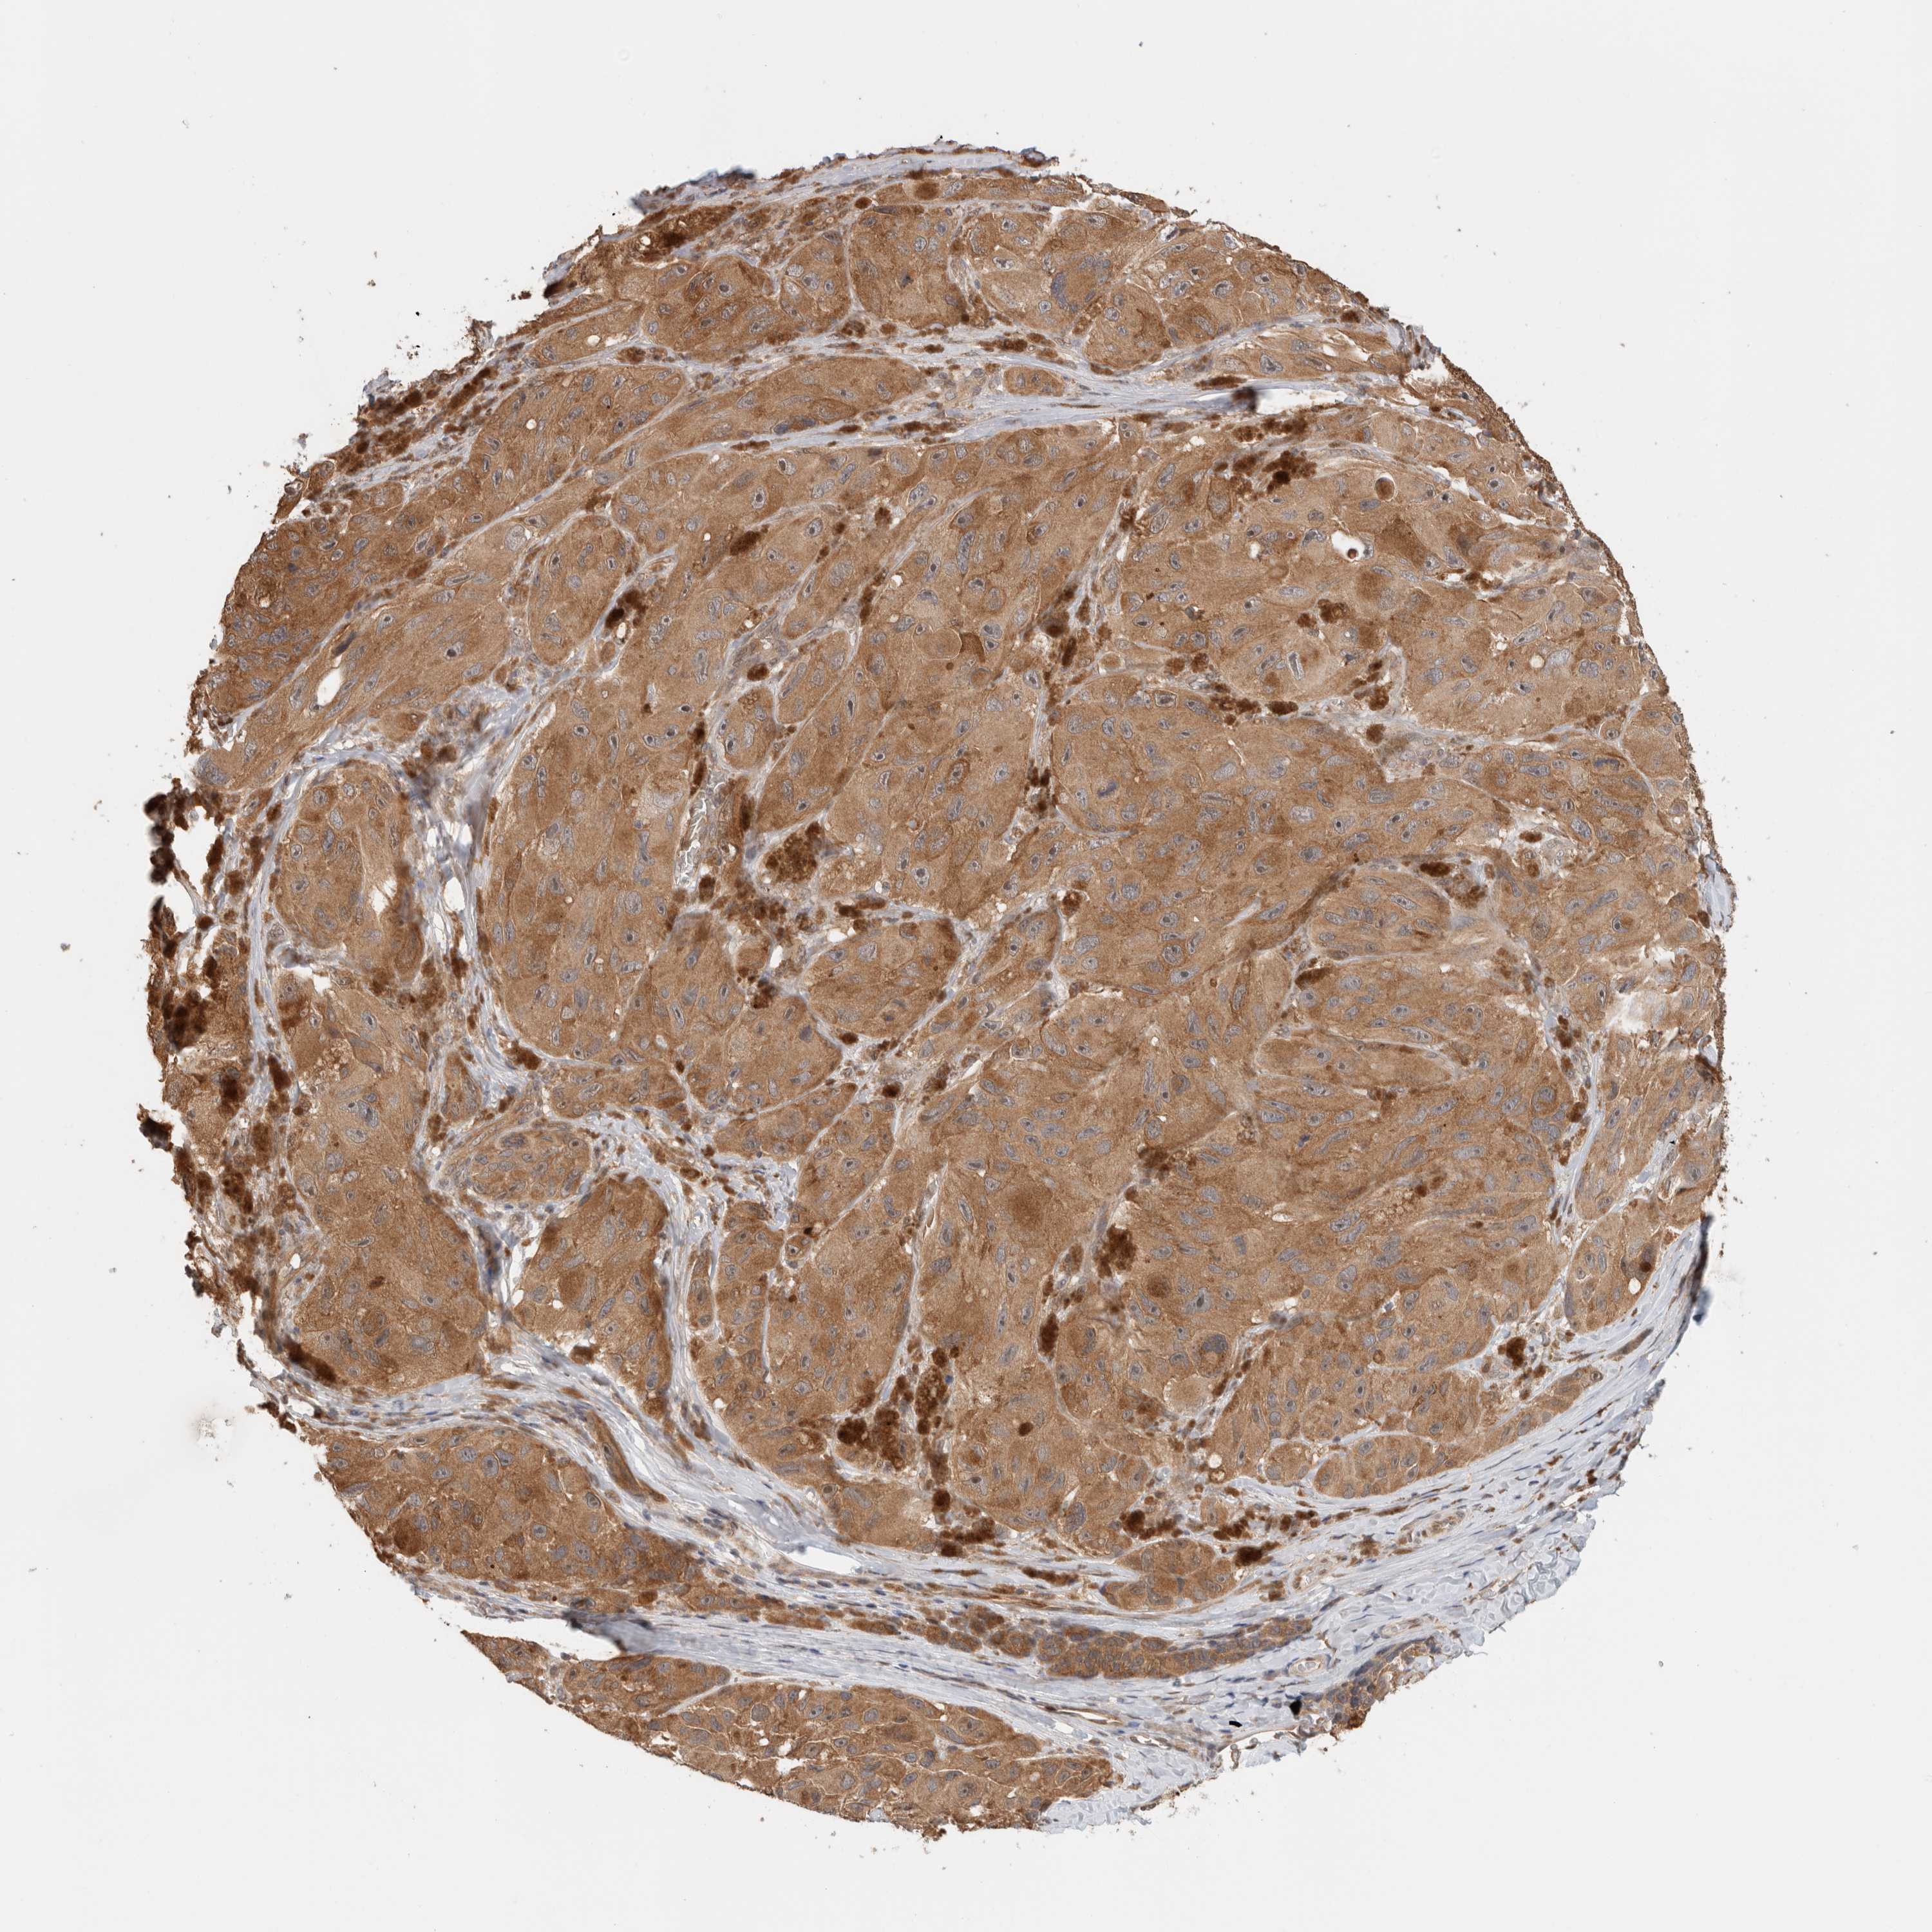

MELANOMA - Protein expressioni

A mouse-over function shows sample information and annotation data. Click on an image to view it in a full screen mode. Samples can be filtered based on level of antibody staining by selecting one or several of the following categories: high, medium, low and not detected. The assay and annotation is described here.

Note that samples used for immunohistochemistry by the Human Protein Atlas do not correspond to samples in the TCGA dataset.

Antibody stainingi

Antibody staining in the annotated cell types in the current human tissue is reported as not detected, low, medium, or high, based on conventional immunohistochemistry profiling in selected tissues. This score is based on the combination of the staining intensity and fraction of stained cells.

Each image is clickable and will lead to virtual microscopy that enables deeper exploration of all samples and also displays staining intensity scores, fraction scores and subcellular localization as well as patient and tissue information for each sample.

Staining

High

Medium

Low

Not detected

Intensity

Strong

Moderate

Weak

Negative

Quantity

>75%

75%-25%

<25%

None

Location

Nuclear

Cytoplasmic/membranous

Cytoplasmic/membranous,nuclear

Malignant melanoma, NOS

Malignant melanoma, Metastatic site